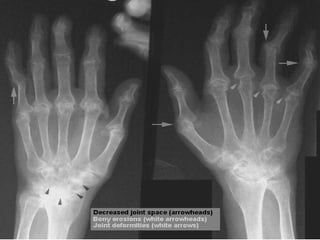

Hand X-ray- RA Describe? Bony erosions Joint deformities Reduced joint space Dx? Rheumatoid arthritis 2 abnormalities in CXR? pleural effusion pulmonary fibrosis Caplan’s syndrome (presence of rheumatoid lung nodules in combination with pneumoconiosis) Why need lateral cervical spine X-ray? Atlanto-axial subluxation   threaten cord * heart: pericardial rub, murmur (AR)

Hand X-ray- RADescribe? Bony erosions Joint deformities Reduced joint space Dx? Rheumatoid arthritis 2 abnormalities in CXR? pleural effusion pulmonary fibrosis Caplan’s syndrome (presence of rheumatoid lung nodules in combination with pneumoconiosis) Why need lateral cervical spine X-ray? Atlanto-axial subluxation  threaten cord * heart: pericardial rub, murmur (AR)